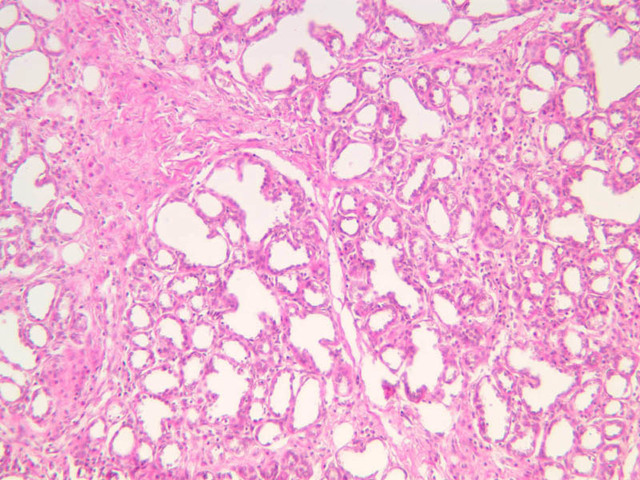

Secretory Phase

This phase occurs on days 15 to 27 and corresponds to the ovarian luteal phase characterized by rising levels of progesterone. The epithelial cells begin to secrete a mucoid fluid rich in nutrients, especially glycogen. The glands become highly coiled and folded and toward the end, very distended. The density of the stroma lessens as it becomes edematous. (slides B-99 [2.5x, 10x, 20x, 40x] [2.5x, 10x, 20x, 40x]; B-100 [1x, 2.5x] [2.5x, 10x, 20x, 40x] [2.5x, 10x, 20x, 40x])